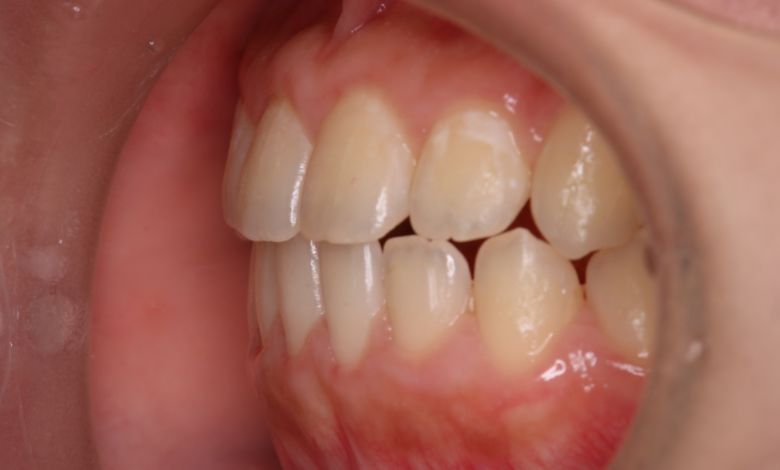

他院にて上下左右4本の抜歯を前提とした矯正治療を提案されていました。上顎・下顎ともに歯列弓が狭く、

V字型の弓状を呈していたため、叢生(歯の重なり)が強く、噛み合わせにも不調和が見られる状態でした。

上顎歯列はV字型に近く、全体的にアーチが狭窄している状態

上下の咬合関係も不正で、機能的にも審美的にも問題のある状態でした

上下の前歯に強い重なりが見られます。特に上顎犬歯と下顎前歯のズレが顕著で、自然な咬合が形成されていない